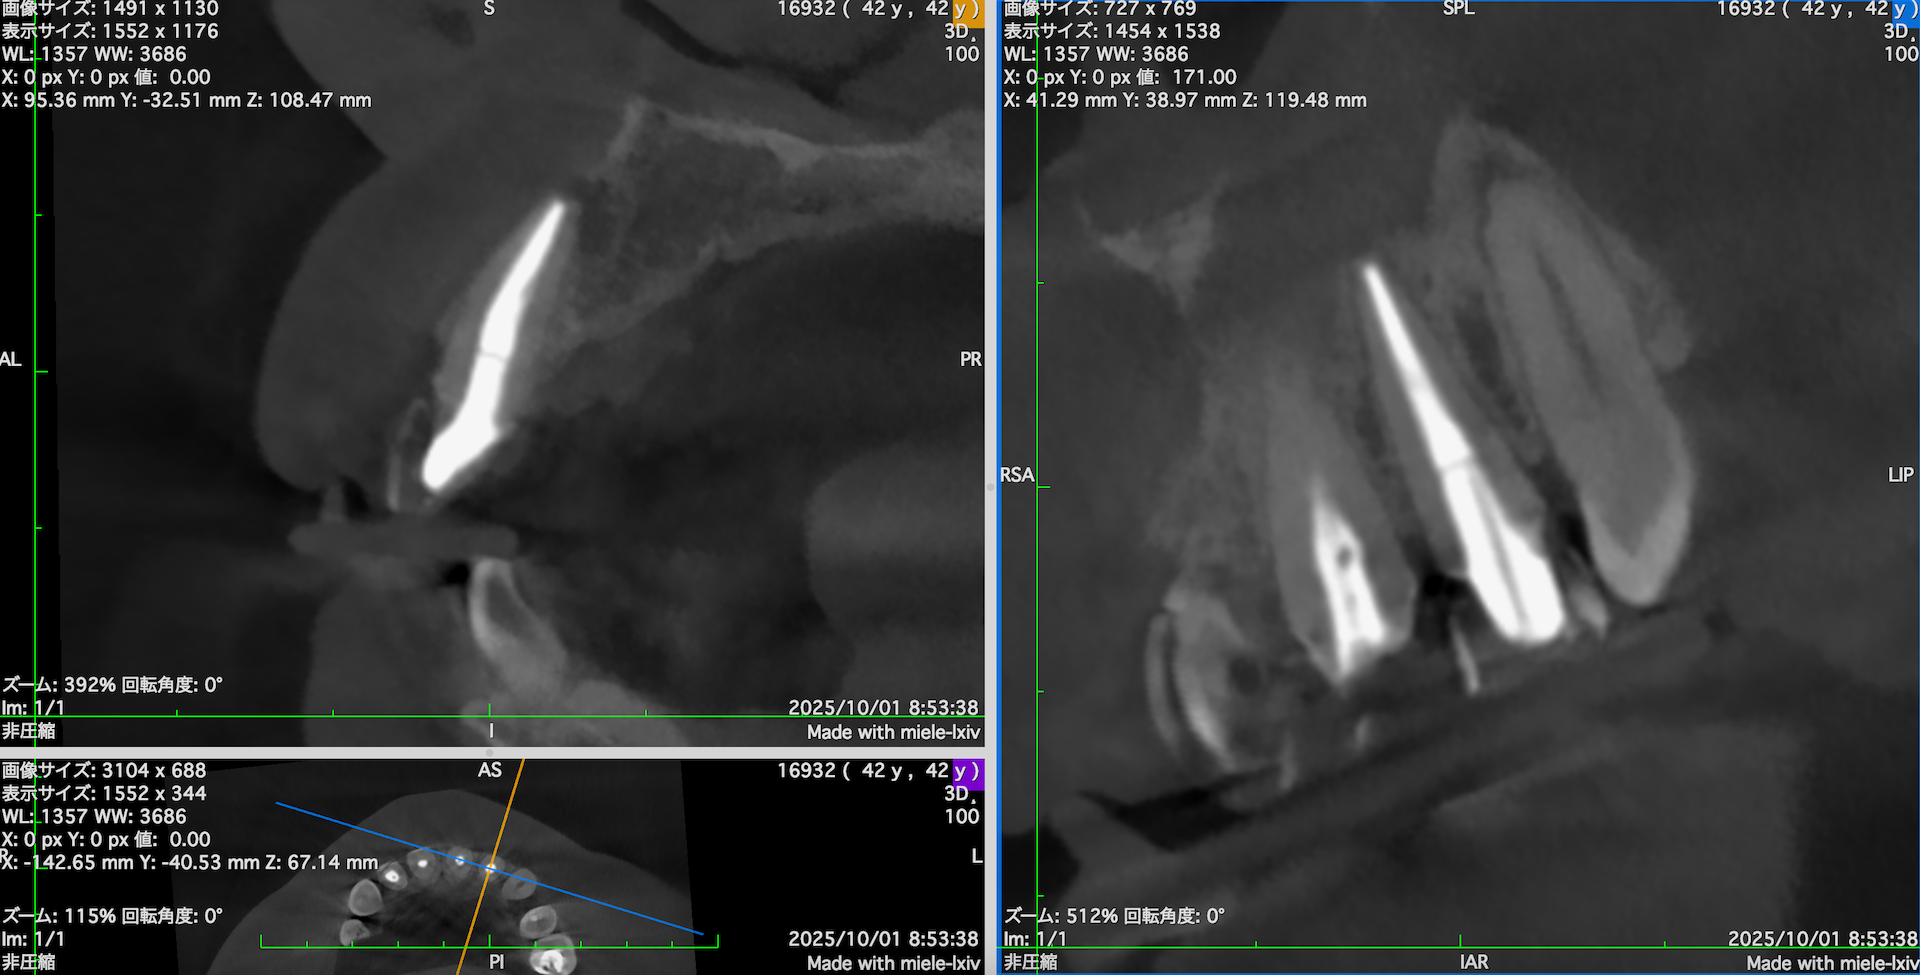

そこで、

CareStream(日本ではヨシダ社)のCBCTなら以下のようにMPR(Multi-Planar Reconstruction)画面を作成することができる。

それを過去のそれと比較してみた。

#7

↓

#10

このMPR画像からこの患者さんは#7,10ともに外科治療など要らないということがわかるだろう。

無論、検査の結果からそれは必要はないと言えるが、

客観的に不要であるということを患者さんに伝えるにもこの画像機能(MPR画像)は非常に有効である。

ということで今日は、このMPR画像機能について論じてみた。